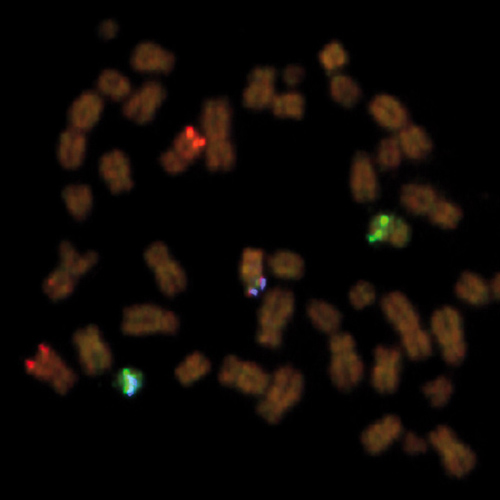

Liposarcoma stained using DDIT3 (12q13) Break – XL for BOND (KBI-XL015).

The DDIT3 (12q13) Break - XL for BOND FISH probe detects genomic translocations involving the DDIT3 gene. DDIT3 (12q13) Proximal - XL and DDIT3 (12q13) Distal - XL are optimized to detect genomic regions proximal and distal to break points in the DDIT3 gene region.

When combined, both probes are used to detect translocations involving the DDIT3 gene at 12q13.